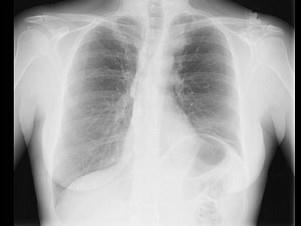

问题 71岁,女,发现颈部淋巴结肿大,胸片和CT检查如图,请选出最可能的诊断 ( )

选项 A、肺癌 B、神经源性肿瘤 C、淋巴瘤 D、淋巴结核 E、结节病

答案 C